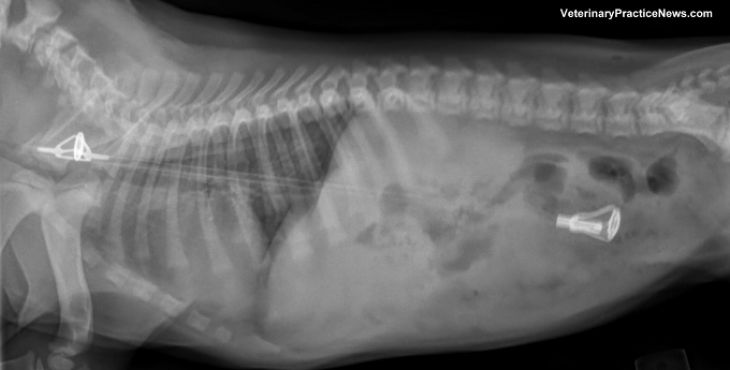

Zubná protéza

Buldog menom Princ Edward prehltol zubnú protézu svojho pána, keď objavil misku spolu so zubami a zmrzlinou.

(Zdroj: Woodstock Veterinary Clinic via VetmMedAZ)